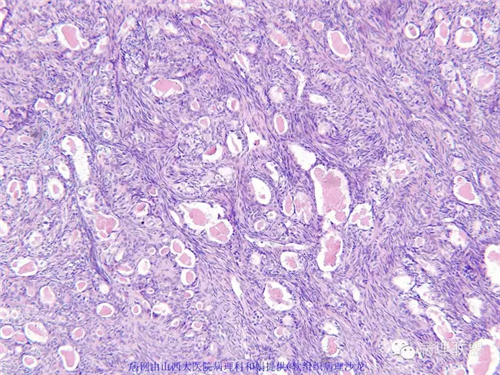

M,57岁,右膝关节外侧皮下肿物10余年,活动度好。

本例形态学上是非常典型的双相型滑膜肉瘤,滑膜肉瘤临床上大部分表现为生长缓慢的肿瘤。以青壮年多见,主要发生于四肢大关节附近,也可见于其他少见部位,如肺、肾等实质器官,形态学分为5种类型:单相纤维型、单相上皮型、双相型、低分化梭形细胞型和小细胞型。有文献报道个别患者有长达20年的病史。